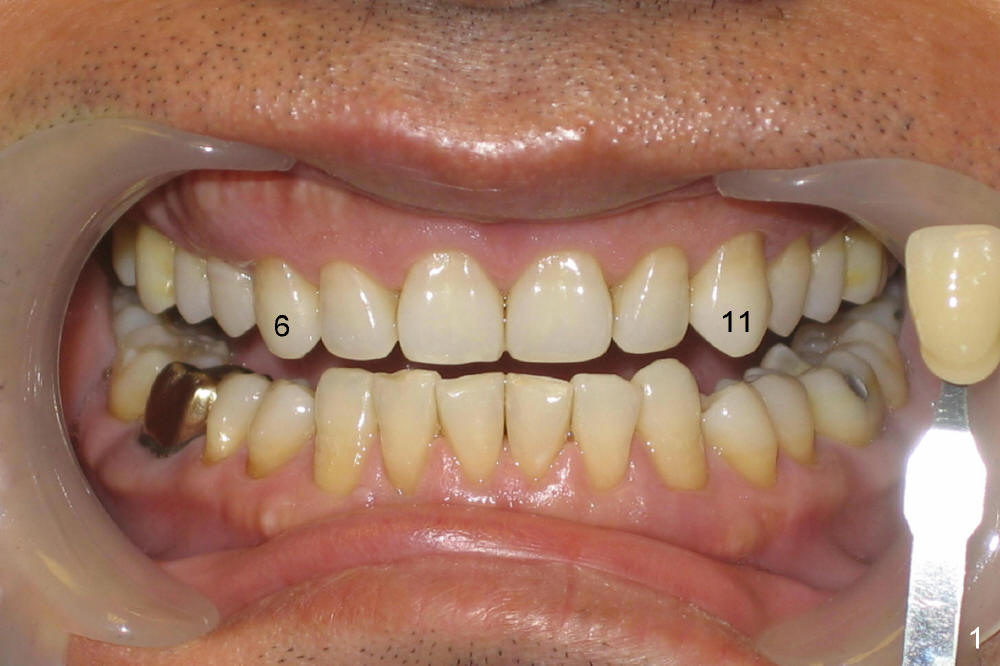

A male patient had trauma to the tooth #6 at the age of 13.  The affected tooth has remained asymptomatic for more than 30 years (Fig.1).   X-ray reveals an oblique root fracture (Fig.2 >) with radiolucency in the mesial alveolus (*, apparently normal trabecular pattern).  Six years later (Feb. 2011), an acute infection develops (Fig.4 *).  It requires incision & draining and antibiotic.  At that time, the trabecular pattern disappears around the fracture line mesially (Fig.3 *).  Four months later cone beam CT shows bone loss between #6 and 7 (Fig.5 *).  Root canal therapy is done as a palliative measure (Fig.6 R; C: Cavit).  Three months later, MTA (mineral trioxide aggregate) is placed in the coronal canal next to the fracture line (Fig.7 M).  It is hoped that MTA can promote nearby bone and cementum to regenerate to seal the fracture line.  Four months after MTA application, there is no sign of bone regeneration (Fig.8).  Bone is lost for approximately 7 mm.

The tooth is discolored probably due to the side-effect of MTA(Fig.9; photo taken 9 months post-MTA).  The mesial gingiva recedes (*).  There is mild persistent pain with purulent discharge mesiobuccally (Fig.10 >).  The corresponding pocket remains 7-8 mm deep in spite of root canal therapy and MTA.